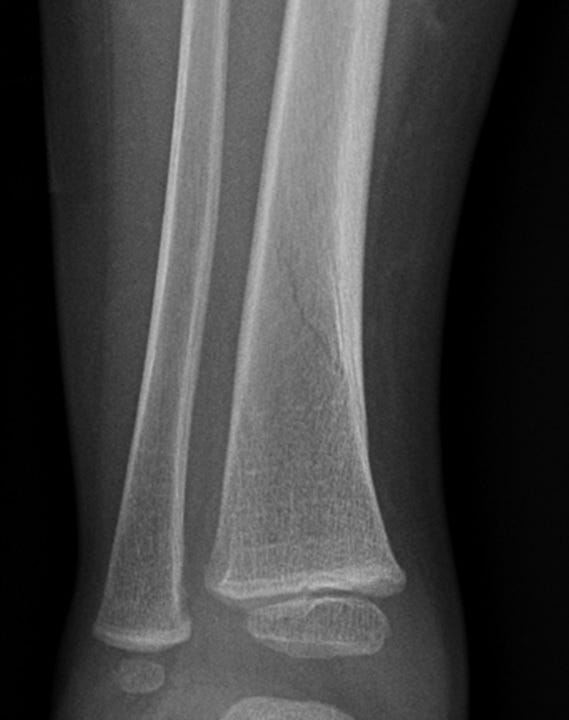

Under the age of four a relative common cause of a limp is the Toddler fracture, a spiral fracture of the tibia or fibula caused by stress on juvenile bone because of “excessive”walking.

Figure 2. Toddler fracture of the distal tibia.